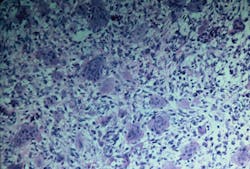

Figure 2

Significant microscopic characteristics: CGCG is noted for the many multinucleated giant cells that are found within the tissue specimen. The multinucleated giant cells are within a sea of spindle-shaped mesenchymal cells and found in areas of hemorrhage.

The giant cells may vary in size and number with scattered placement, or they may be concentrated within distinct areas of the specimen. Newly formed bone may be present within the specimen as well. The more aggressive type of CGCG is not distinguishable from the nonaggressive type by microscopic examination (see Figure 2).